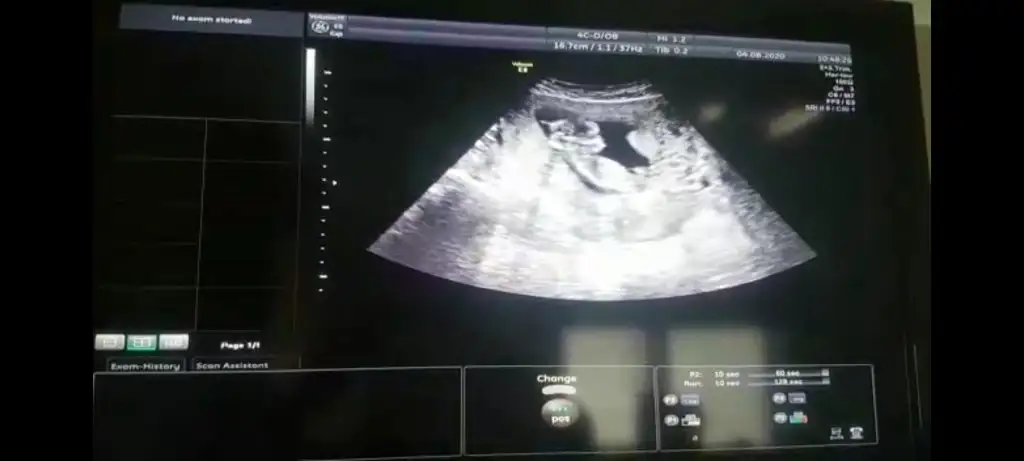

Erkek gibi sanki 13 hafta olursa tekrar paylaşın net değil USG emin olamadimMerhaba 11+6 günlük bebeğim. Bana da tahmin yapabilir misiniz? Eki Görüntüle 2680665

Erkek bebişMerhaba, 12. haftadan ultrason görüntülerimiz. Yorum yaparsanız çok sevinirim.Eki Görüntüle 2678844 Eki Görüntüle 2678845 Eki Görüntüle 2678846 Eki Görüntüle 2678844 Eki Görüntüle 2678845 Eki Görüntüle 2678846 Eki Görüntüle 2678844 Eki Görüntüle 2678845 Eki Görüntüle 2678846 Eki Görüntüle 2678846 Eki Görüntüle 2678844 Eki Görüntüle 2678845 Eki Görüntüle 2678846 Eki Görüntüle 2678844 Eki Görüntüle 2678845 Eki Görüntüle 2678846

Bana da öyle geldi bi de erkek olsa belli olurdu bu hafta dedi cogu kisi. Kız daha geç görünüyormuş bakalım ne cikacak iki hafta sonra yazarımKız gibi sanki